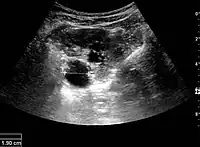

Complex cysts can have membranes dividing the fluid-filled center with internal echoes, calcifications or irregular thickened walls. The complex cyst can be further evaluated with Doppler US, and for Bosniak classification and follow-up of complex cysts, either contrast-enhanced ultrasound (CEUS) or contrast CT is used (Figure 6). The Bosniak classification is divided into four groups going from I, corresponding to a simple cyst, to IV, corresponding to a cyst with solid parts and an 85–100% risk of malignancy.[1] In polycystic kidney disease, multiple cysts of varying size in close contact with each other are seen filling virtually the entire renal region. In advanced stages of this disease, the kidneys are enlarged with a lack of corticomedullary differentiation (Figure 7).[1]

Figure 7. Advanced polycystic kidney disease with multiple cysts.[1]